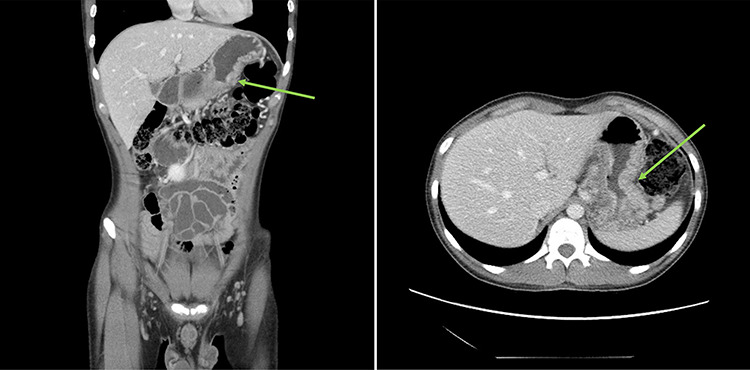

Urgent gastroscopy revealed a giant gastric ulcer in the antrum (Fig. 1) which was biopsied and sent for pathological investigation. The ulcer displayed no bleeding stigmata. He was started on eradication therapy for Helicobacter pylori. Pathology revealed a signet ring adenocarcinoma of the stomach (Fig. 2A and B). A computerized tomography (CT) scan (Fig. 3) showed a large mass in the distal stomach, and the ensuing positron emission tomography (PET) scan (Fig. 4) showed enlarged D1 perigastric lymph nodes with no obvious metastatic disease.

Figure 3.

: (A and B) CT scans (coronal and axial views) showing a large mass in the distal stomach (green arrows).